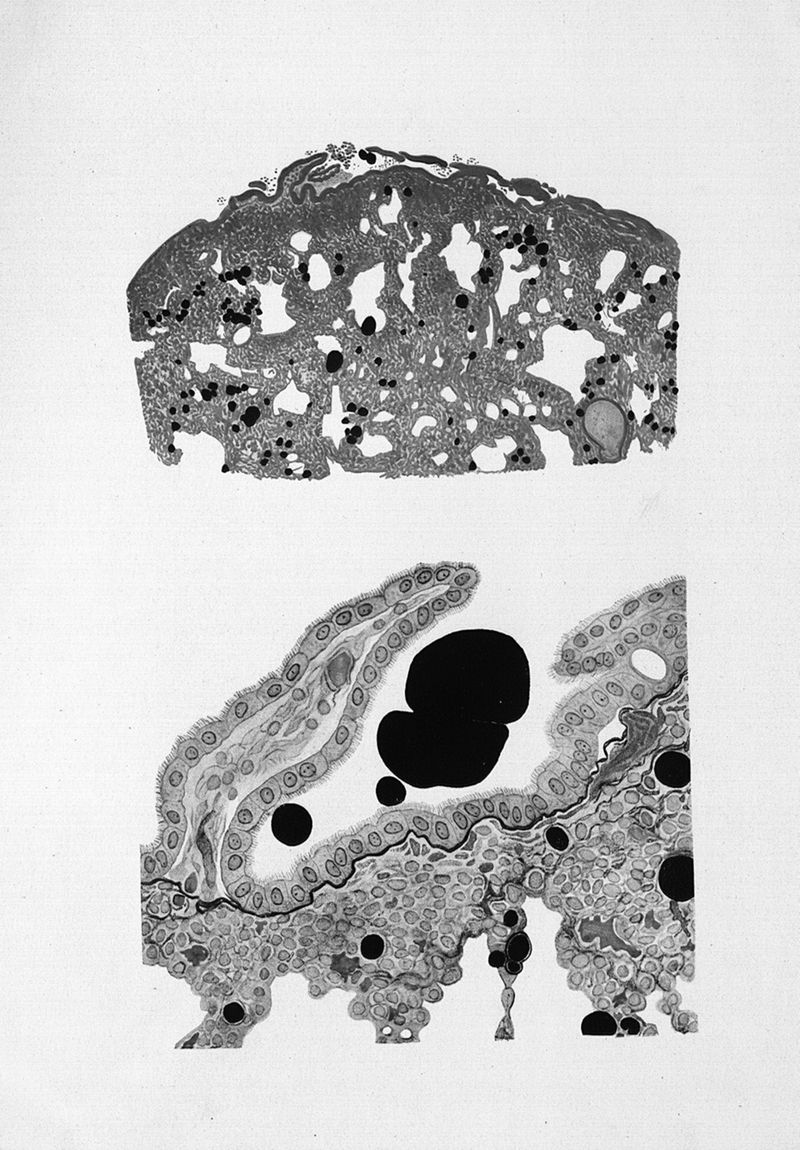

Binet, Léon.

Titres et travaux scientifiques

Paris, Masson et Cie, 1930.